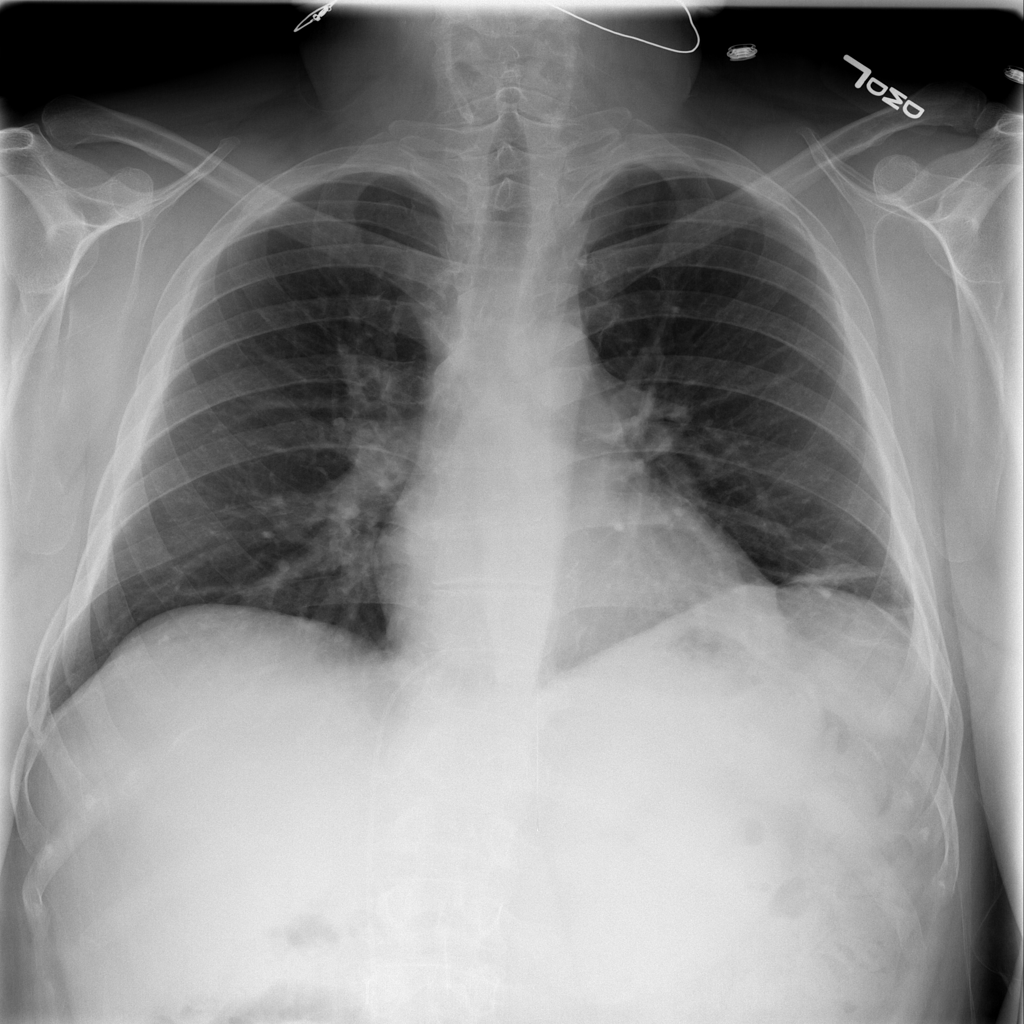

PAT-3384 · IMG-054Atelectasis

PAT-3384 · IMG-054

AP